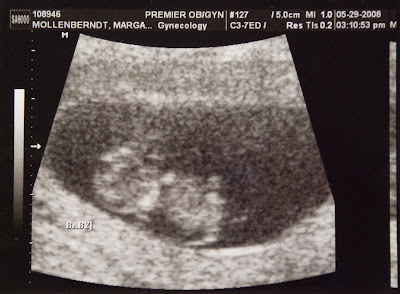

Of course, Mark wasn't there (this was compeltely unexpected appointment) but we called him on my cell phone so he could hear the heart beat (an "excellent" 188 beats per minute) and the tech took our baby's first picture!

About the size of a large grape or small strawberry - our baby seems to be doing just fine! "Kidlet" was very wiggly and squirmy. "Kidlet" did not care for the poke of the ultrasound wand - every time he/she was poked to be photographed, he/she wiggled to try and get away!! In the pic, you will see him/her laying on his/her tummy. Head is over to the left, one arm is up by their face, and you can see one of the legs down on the right.